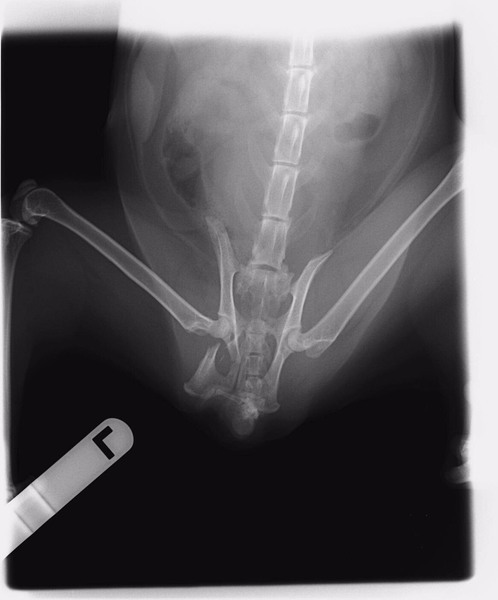

| 里親募集する理由 | 元は野良猫ちゃんです 車に跳ねられたようで、動けなくなっておりました。 保護しレントゲンの結果、骨盤骨折でした。 皆さんに助けられ、時間は経ってしまいましたが手術を無事乗り越えました。 今は元気に走り飛び跳ねております。 心配していた腸の圧迫も大丈夫で、トイレも今まで通り自分でしています。 |